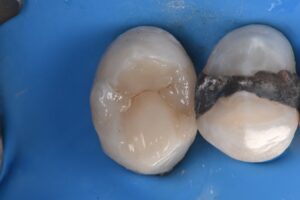

Extreme DME case using the Rhondium DME wedge in sequence with the Garrison Compositight system with a supercomposite placed incrementally to support what little is left of this extremely-compromised second bicuspid.

#VocoGrandioSO #RhondiumDME #GarrisonCompositight